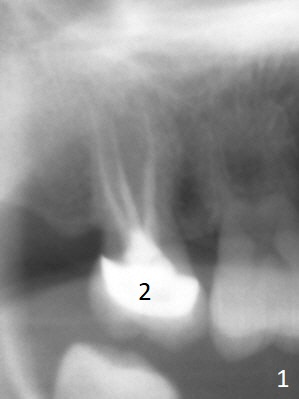

A 58-year-old woman has had RCT done at #2 for several years. The roots are trifurcated with sufficient bone height (Fig.1-3). Recently the tooth becomes symptomatic with formation of a distal fistula (Fig.4). After extraction, the septum (Fig.5 S) may be wide enough for initial drill (Fig.6). If not, resection the thin part of the septum (Fig.7 red line, with small or medium Rongeur) and use the initial drill (Fig.8). Anyway, take PA immediately to avoid sinus membrane perforation. If possible, adopt single drill technique.